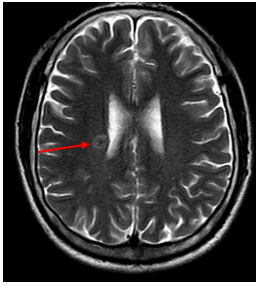

-         MRI sọ não:

Hình 4. Trên phim chụp MRI sọ não: Rải rác trong nhu mô trên và dưới lều có các nốt ngấm thuốc, lớn nhất vị trí cạnh não thất bên bên phải đường kính ~11mm – Theo dõi tổn thương thứ phát

Cộng hưởng từ sọ não:

Sau 6 tháng điều trị: Nhu mô não vùng trên và dưới lều tiểu não: hình dạng và cấu trúc bình thường, tín hiệu đồng nhất, ranh giới chất trắng và chất xám rõ. Không thấy tổn thương khu trú hoặc lan tỏa.